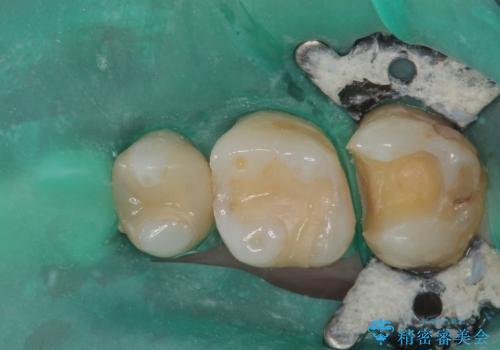

最新の症例

Latest cases